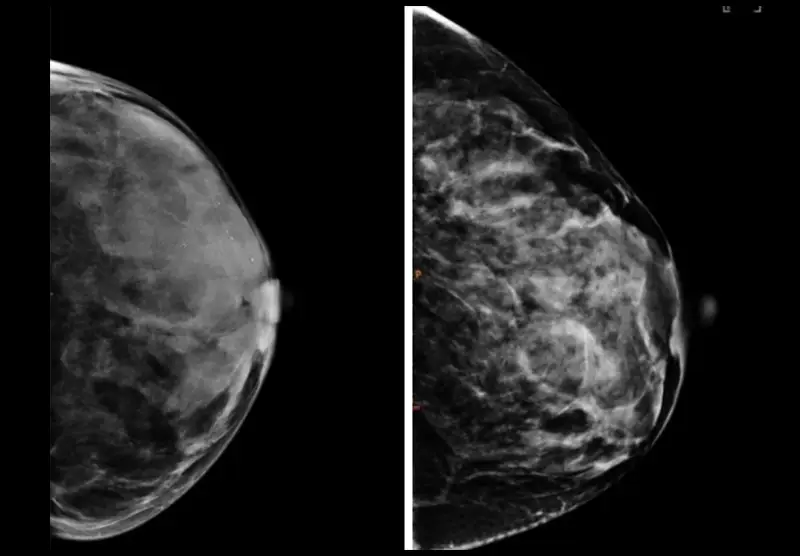

Mammogram images of two breasts that show different breast textures.

Breasts with the same density can have vastly different breast textures, as seen in the mammography above. Images courtesy of Despina Kontos/Columbia.

A mammogram can reveal whether a woman has dense breast tissue, a feature linked to a higher risk of breast cancer that requires extra screening. However, findings from a new study published in Radiology suggest that six different breast texture patterns, which can also be seen on mammograms, do a better job of predicting breast cancer than breast density.

“Given that women with the same breast density can have substantially different texture patterns, our analysis provides important additional information for estimating breast cancer risk,” Dr. Kontos says.